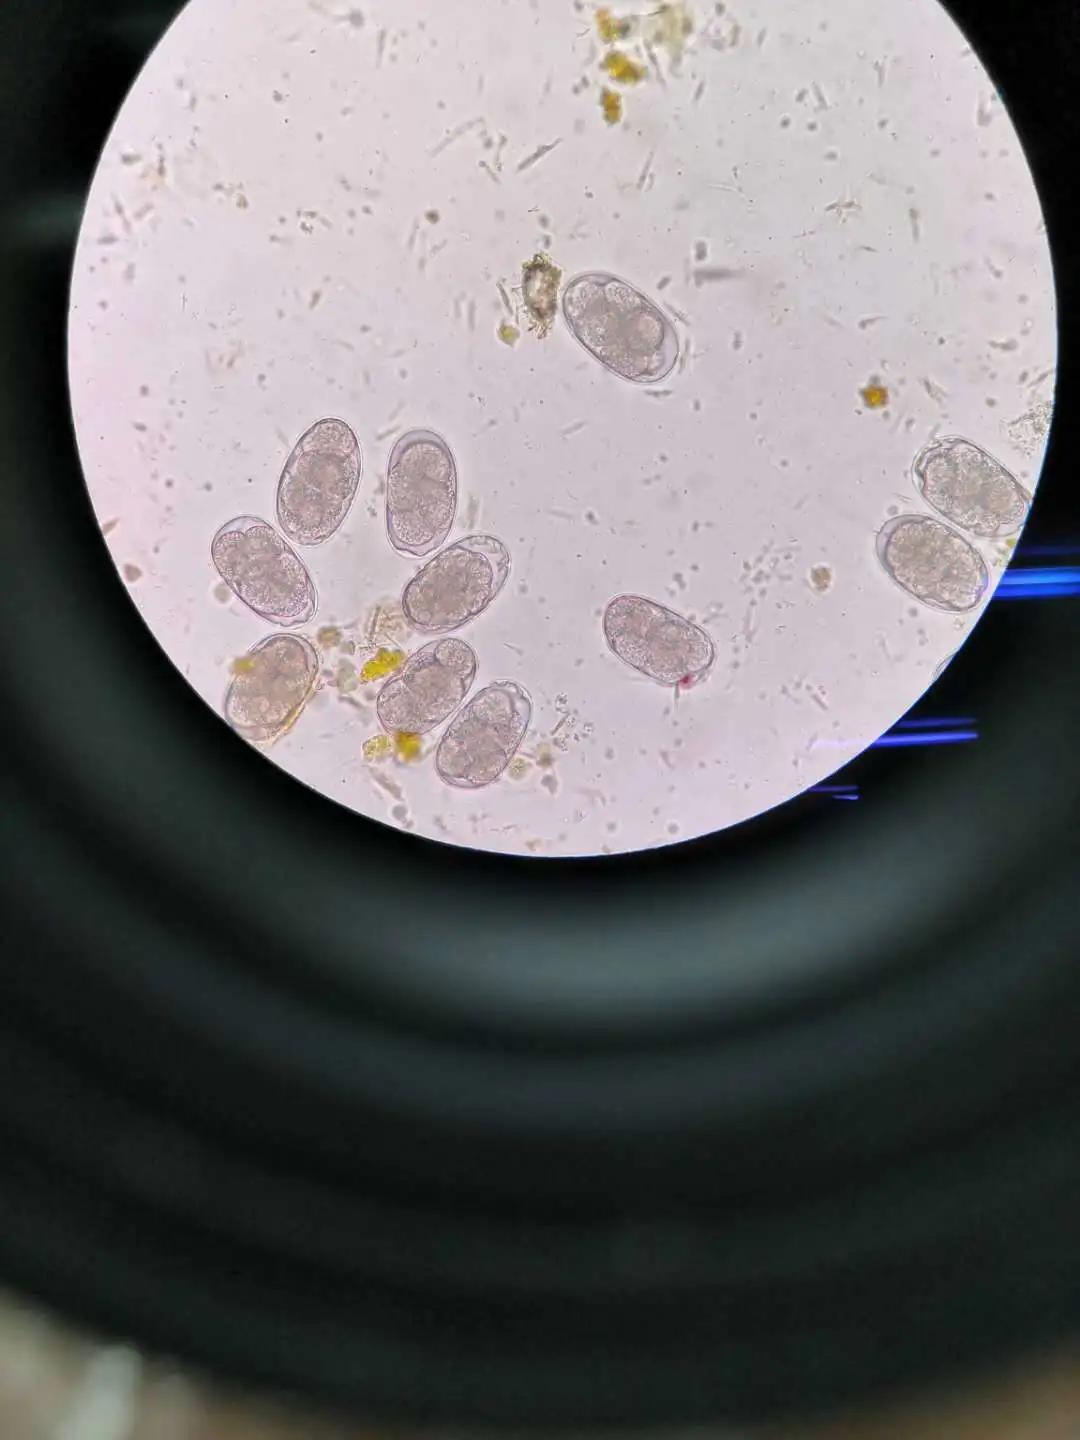

為了鼓勵(lì)“不怕臟不怕臭,堅(jiān)持不懈”這種精神,科室特別設(shè)立“找蟲卵紅包”,找到蟲卵者,都會(huì)得到獎(jiǎng)勵(lì),大大提高了蟲卵的檢出率。我們不會(huì)忘記渾身大便氣息,苦苦尋找蟲卵的青春歲月。2020年上半年檢驗(yàn)中心寄生蟲檢出率如下:大便常規(guī)3626人次,找到鉤蟲卵11個(gè),藍(lán)氏賈第鞭毛蟲滋養(yǎng)體3個(gè),人腸道滴蟲2個(gè),人芽囊原蟲包囊54個(gè)。

鉤蟲卵

蛔蟲卵

人芽囊原蟲包囊